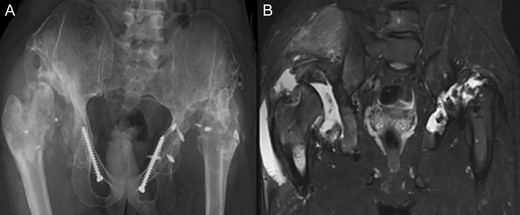

(A + B): (2019) (A) x ray of the pelvis after a 10 year follow up. The right head further migrated und subluxated and femoral head necrosis is visible, new bone formation at the ileum stabilizing the joint. At the left side high dislocation of the hip with fully necrosis of the head and ankylosis of the hip joint. (B) MRI showing hip effusion around the joint which is painless.

At this stage patient’s walking ability was already limited due to muscle weakness and rubbing in the hip joints, so we recommended no further walking and weight bearing. Further follow-up at 5 years (Fig. 7) and 10 years (Fig. 8A) until today showed radiologically complete absorption of the left femoral head and the right hip continuously moving cranially creating a false acetabulum and a flattened femoral head. At final follow up the patient was in a wheel chair but able to bend both hips up to 110 degrees without noticeable pain, he could stand up with help for a short time and showed a massive Charcot joint with effusion (Fig. 8B) of the right hip without further clinical implications.